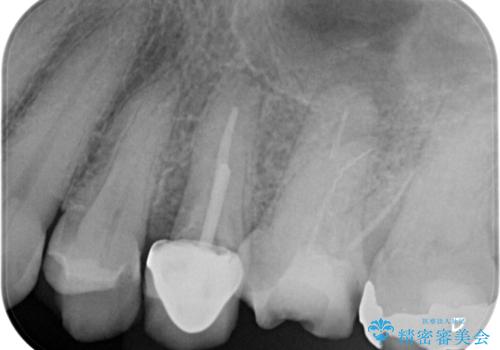

【破折ファイル除去】他院で折れた根管治療の器具をとってほしい

- 他院で折れた根管治療の器具をとってほしいという主訴で来院されました。

マイクロスコープで根管内を観察すると、除去できる状態だったため破折ファイル除去を行いオールセラミッククラウンにて修復治療しております。

通常、根尖湾曲の先にあるファイルは無理に取るより外科治療によりアプローチすることを推奨しています。